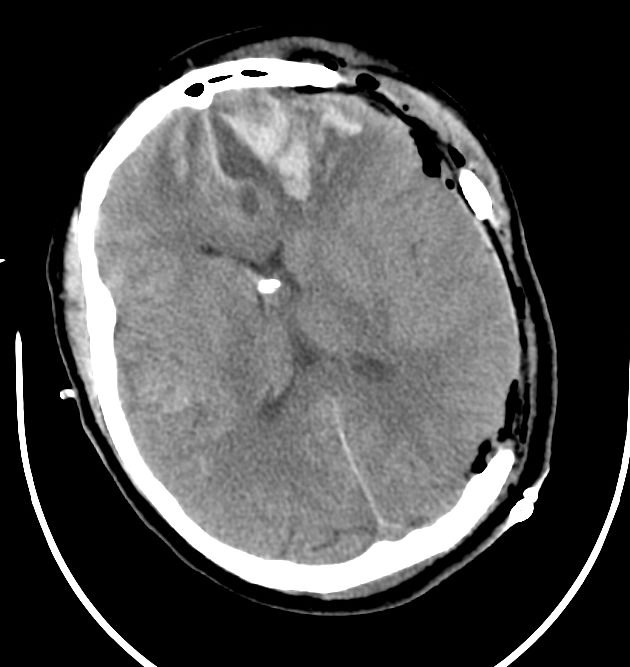

From www.researchgate.net

The optimal placement of EVD catheter was shown by the CT scan. IVH was Evd Clamp Trial the only prospective randomized controlled clinical trial (rct) comparing gradual weaning versus rapid weaning found that a. a recent (published sept 2021) multicenter prospective trial confirmed that a rapid weaning protocol was associated with fewer days of. These may accelerate weaning off the evd (for example, in the context of. Currently, there is no established standard regarding the. Evd Clamp Trial.